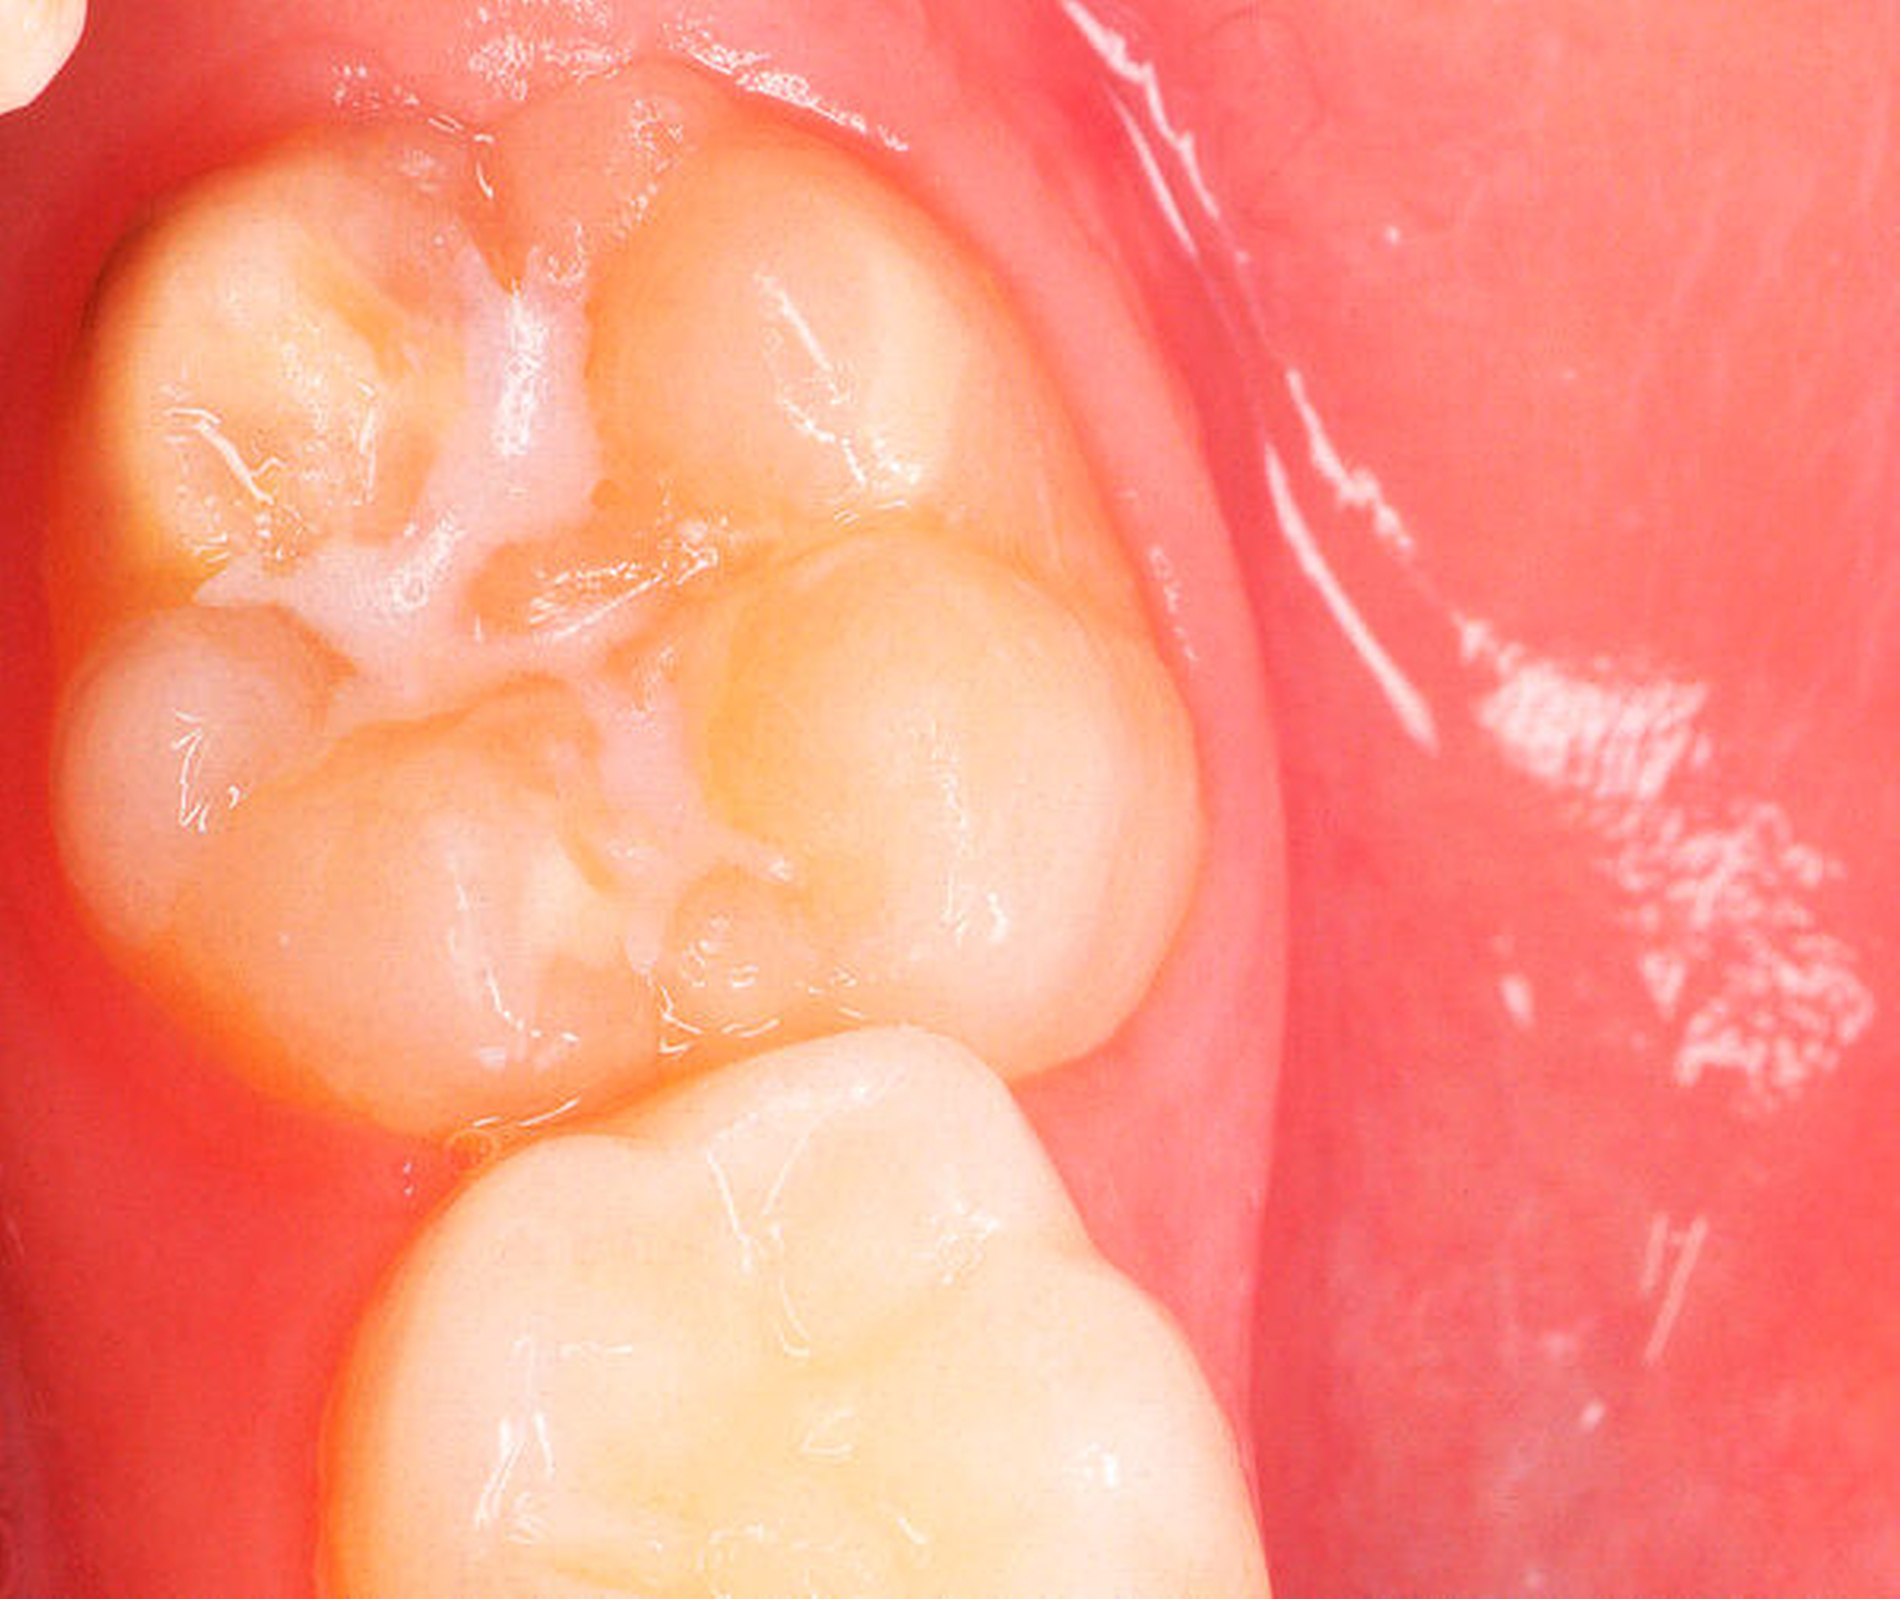

Die Ausprägung der Mindermineralisation kann stark variieren (Abbildungen 3 und 4). Klinisch zeigen sich an den betroffenen Zähnen unterschiedlich starke Verfärbungen beziehungsweise Opazitäten bis hin zu ausgeprägten Schmelzverlusten. So kann die Mineralisationsstörung im Bereich der Molaren auf einzelne Bereiche beschränkt sein, das Fissurenrelief einbeziehen oder sich über die gesamte Glattfläche erstrecken [Koch et al., 1987]. Bei den Inzisiven ist die Mindermineralisation bukkal zu finden. Geringgradig betroffene Zähne sind dabei eher durch weiß-gelbliche oder gelb-braune, unregelmäßige Verfärbungen gekennzeichnet, schwere Hypomineralisationsformen weisen dagegen abgesplitterte oder fehlende Schmelz- und/oder Dentinareale unterschiedlichen Ausmaßes auf.

Sind bei einem Patienten mehrere Molaren betroffen, so kann es auch hier zu Variationen kommen. Dementsprechend kann es sein, dass bei einem Molaren kleine, intakte Opazitäten zu finden sind, während an einem anderen Molaren große Teile des Schmelzes bereits kurz nach dessen Eruption einbrechen [Weerheijm, 2004].

Bildgruppe Abb. 7–14:Grade des MIH-Treatment-Need-Index im klinischen Erscheinungsbild